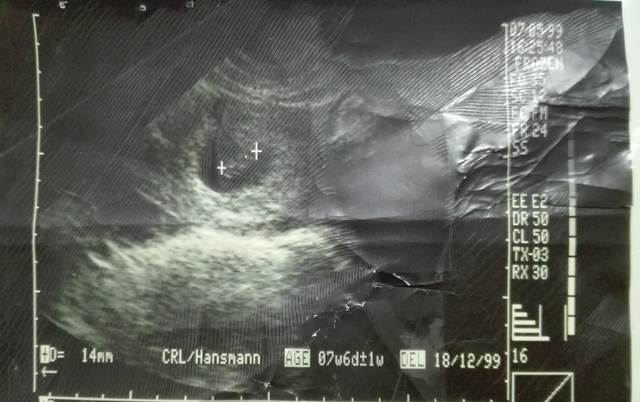

Mi primer ecografia

Fue una linda sorpresa para mi mamita,teniendo 3 0 4 semanas de embarazo donde pudo observar como me iba formando en su barriguita